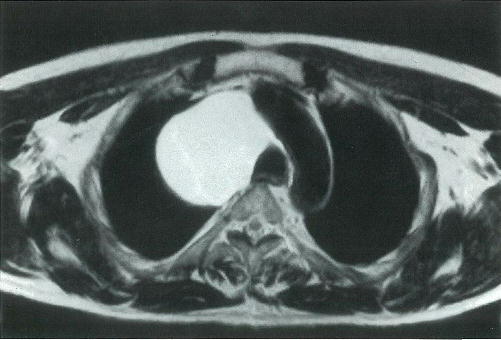

43歳の男性。健康診断の胸部エックス線写真で腫瘤陰影を指摘されて来院した。胸部単純MRIのT1強調像とT2強調像とを別に示す。

腫瘤の性状として最も考えられるのはどれか。

a 気体

b 漿液

c 線維

d 脂肪

e 石灰

× a

○ b

× c

× d

× e

正解 b

診断 縦隔嚢胞(胸腺嚢胞など)